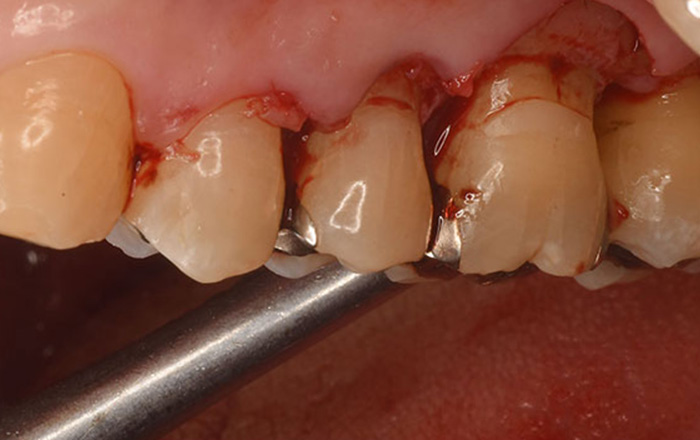

1.バイ菌・歯石を取る、フラップ手術

フラップ手術は、歯ぐきを切開し、歯ぐきの上からの歯周病治療では取れないバイ菌や歯石を除去します。

炎症がある歯周組織を除去し、バイ菌がつきにくい状態を作ります。